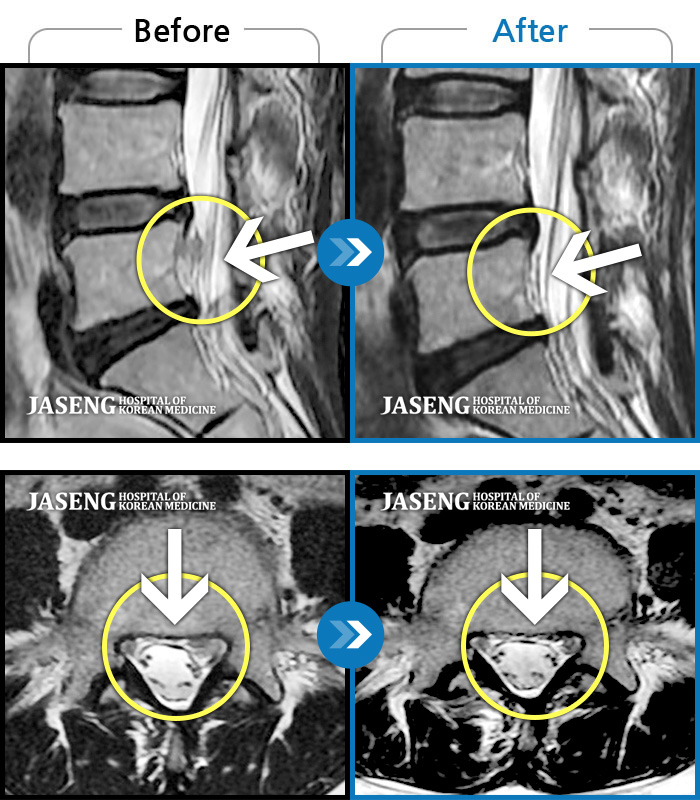

푸쉬업을 여러 번 반복한 뒤 극심한 하요부 통증 및 우측 하지부 저림

2024.03.21 ~ 2024.09.23